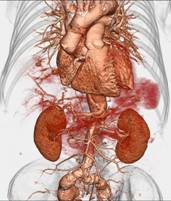

※肝脏、胰腺、肾脏CT-DSA 及灌注功能一站式检查